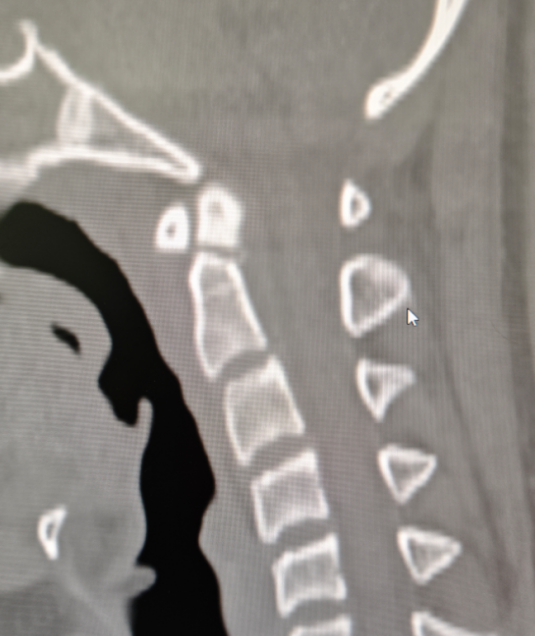

为了把病情摸得更透,脊柱骨伤科当天就安排小王做了寰枢椎 CT 平扫,结果清晰显示:枢椎齿状突骨折,骨折块位置明确,周围可见小骨碎片,但万幸无明显神经压迫。